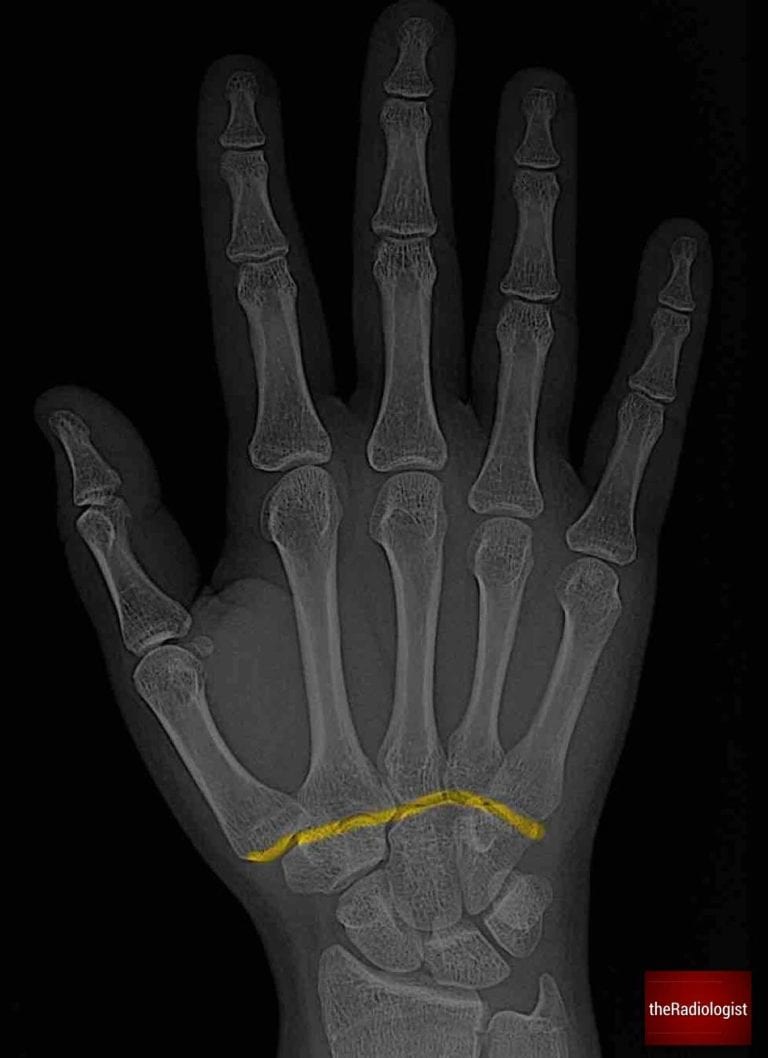

Trace Gilula’s arcs across the proximal and distal carpal rows, watching for any break in these smooth curves. A break could mean a ligament injury or fracture.

Trace all carpal bones making sure there is no subtle fracture.

Trace Gilula’s arcs: disruption of any of these points towards carpal instability or fracture